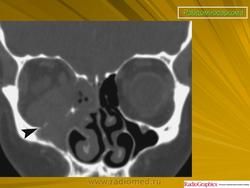

Рабдомиосаркома — чрезвычайно агрессивная опухоль орбиты, является наиболее частой причиной злокачественного роста в орбите у детей. Мальчики болеют почти в 2 раза чаще. Источником роста рабдомиосаркомы являются клетки скелетных мышц. Выделены три типа опухоли: эмбриональный, альвеолярный и плеоморфный, или дифференцированный. Последний тип встречается редко. У детей до 5 лет чаще развивается эмбриональный тип опухоли, после 5 лет — альвеолярный. Как правило, рабдомиосаркома состоит из элементов нескольких типов (смешанный вариант). Точный диагноз можно установить только на основании результатов электронной микроскопии.

Излюбленная локализация опухоли — верхневнутренний квадрант орбиты, поэтому в процесс рано вовлекаются мышца, поднимающая верхнее веко, и верхняя прямая мышца. Птоз, ограничение движений глаза, смещение его книзу и книзу кнутри — это первые признаки, на которые обращают внимание как сами больные, так и окружающие лица. У детей экзофтальм или смещение глаза при локализации опухоли в переднем отделе орбиты развивается в течение нескольких недель (рис. 20.23, а). У взрослых опухоль растет медленнее, в течение нескольких месяцев. Быстрое увеличение экзофтальма сопровождается появлением застойных изменений в эписклеральных венах, глазная щель полностью не смыкается, отмечаются инфильтраты на роговице и ее изъязвление. На глазном дне — застойный диск зрительного нерва. Первично развиваясь вблизи верхневнутренней стенки орбиты, опухоль быстро разрушает прилежащую тонкую костную стенку, прорастает в полость носа, вызывая носовые кровотечения. Ультразвуковое сканирование, компьютерная томография, термография и тонкоигольная аспирационная биопсия — это оптимальный диагностический комплекс инструментальных методов исследования при рабдомиосаркоме (рис. 20.23, б). Лечение комбинированное. Протокол лечения предусматривает предварительное проведение полихимиотерапии в течение 2 нед, после чего проводят наружное облучение орбиты. После комбинированного лечения более 3 лет живут 71 % больных.